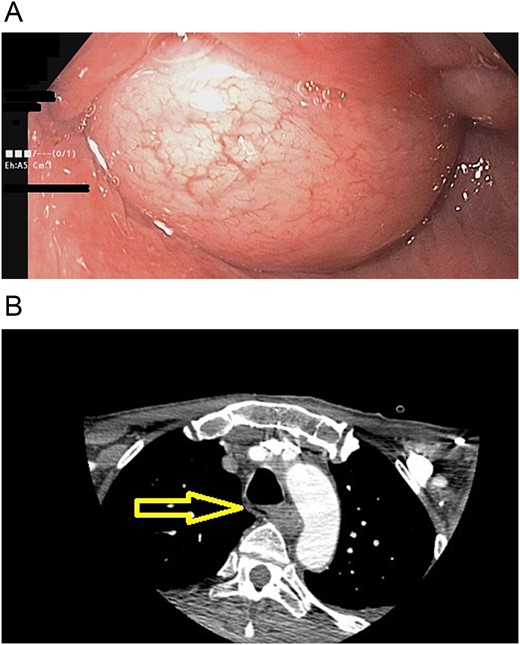

The patient is a 70-year-old male with a past medical history of prostate cancer. He presented with a two-year history of progressive dysphagia. At first, he complained of epigastric pain, nausea, and vomits. In the last three months, he found it increasingly difficult to eat anything solid, until he found it impossible to swallow. Due to this, an upper endoscopy and a contrast-enhanced chest computed tomography (CT) were done at that time, revealing a giant superior esophageal polyp (Fig. 1) 28 cm away from the dental arcade; therefore, surgical resection was recommended. Nonetheless, the patient refused any surgical management.

(A) CT scan: esophageal polyp is seen in the esophageal lumen. (B) CT scan: esophageal polyp completely obstructs but does not invade the esophagus.